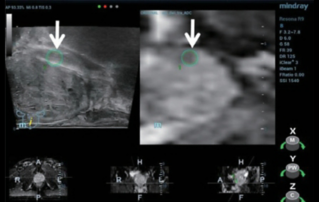

??? ????? ?? ??? ???? ??? ???? ??? ????, ?? ?? ??(PPE)? ??? ??, ? ??, ??? ?? ??? ???? ??? ?? ??? ??????. ???? ???? ??? ??? ??? ?? ??? ???? ?? ?? ?? ???? ?? ?? ??? ?? ???? ???? ?? ?? ?? ??(POC) ? ??? ??? ? ? ?????.